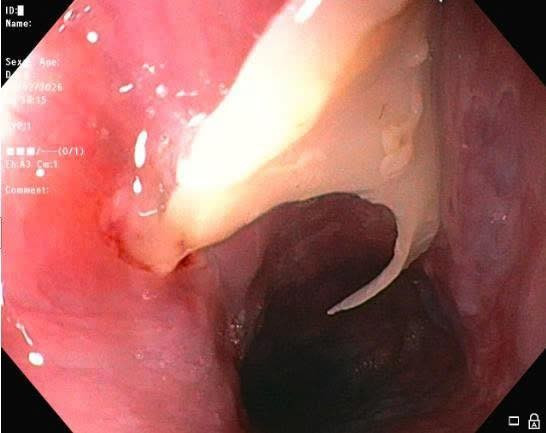

Tại Phòng Nội soi tiêu hóa – Đơn Nguyên thăm dò chức năng, Bệnh viện Đa khoa Đống Đa ThS.BS. Nguyễn Quang Vinh – Trưởng khoa Nội tổng hợp là bác sĩ trực tiếp nội soi cho người bệnh ghi nhận niêm mạc ngay 1/3 thực quản trên có dị vật là mảnh xương sắc nhọn, mắc chặt trong lòng thực quản, nhiều đầu nhọn cắm xuyên vào thành thực quản.

Dị vật trong thực quản bệnh nhân - Ảnh BVCC